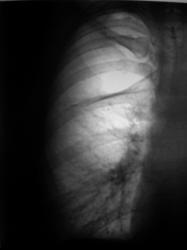

А на боковой рентгенограмме лентовидная тень - это спавшаяся верхняя доля?

видимо да, это лопнувшая и спавшаяся верхняя доля.

Такая картина развивается при длительно существующем пневмотораксе или пневмогидротораксе: на висцеральной плевре образуется фибрин, формируются спайки между висцеральной и париетальной плеврой, фиксирующие легкое, что не позволяет ему расправиться.